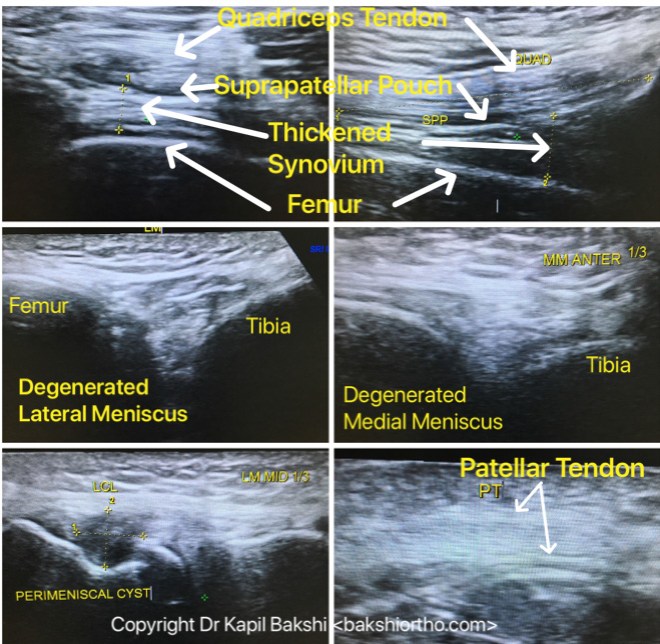

KNEE ULTRASOUND

Pathologies visualized on Ultrasound are Synovitis, Effusion in Suprapatellar Pouch, Disorders of Retinaculum, Meniscus Degenerative and Traumatic Tears, Quadriceps and Patellar Tendinitis and Tendinosis, Baker’s Cysts, Meniscal Cysts and Ganglion.

Meniscal Tears and Bursa under Medial Collateral Ligament

Meniscal Cyst as seen on Ultrasound and MRI Comparison

Patellar Tendinitis

The x-rays are generally normal but Ultrasound can clearly demonstrate the quantum of inflammation, seen closer to tibial tuberosity and patellar ends as in this case.